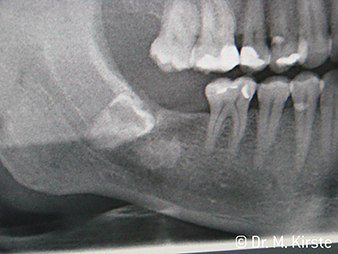

Kątnice WS-91 i WS-91 LG stanowią unikalne połączenie zalet kątnicy i prostnicy chirurgicznej (Zdj. 1). Powiększony kąt pomiędzy uchwytem a główką kątnicy do 45° znacznie ułatwia dostęp do pola operacyjnego zarówno do strony policzkowej jak i okluzyjnej (Zdj. 4). W efekcie radykalnie poprawia się komfort pracy np. podczas ekstrakcji zębów zatrzymanych, a poszerzone pole widzenia dodatkowo czyni zabieg bezpieczniejszym (Zdj. 6 i 7). „Wystarczy, że przekręcę nieznacznie główkę kątnicy i już mogę pracować niezwykle szybko i bezpiecznie w okolicy zębów trzonowych. Zalety nowych kątnic W&H mają szansę pogodzić zwolenników używania prostnic z lekarzami preferującymi kątnice ” Dr. Mario Kriste (Zdj. 2-5).